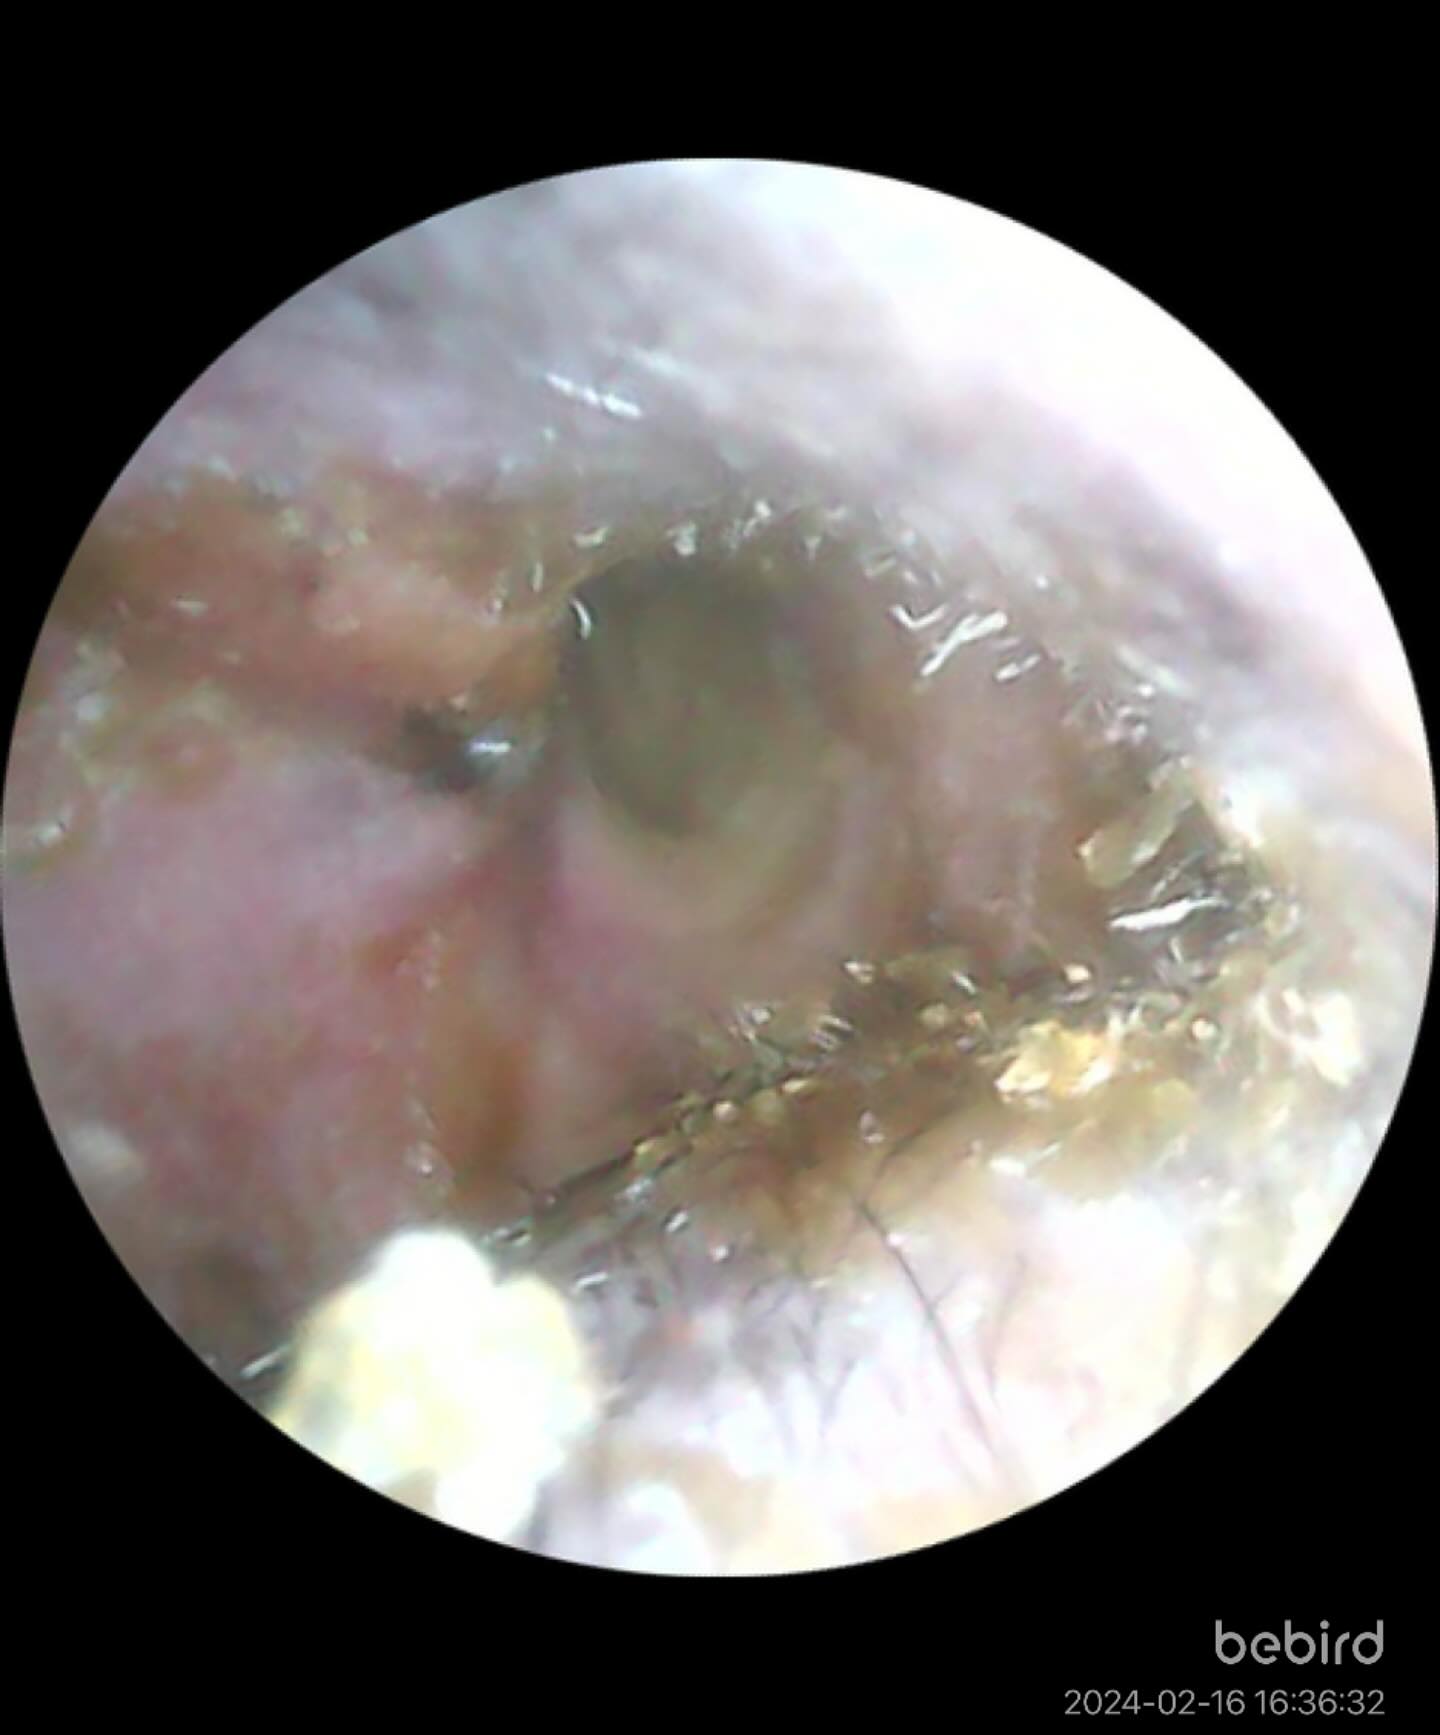

歯周疾患診療

人と同じように犬猫も口腔内環境が重要です。